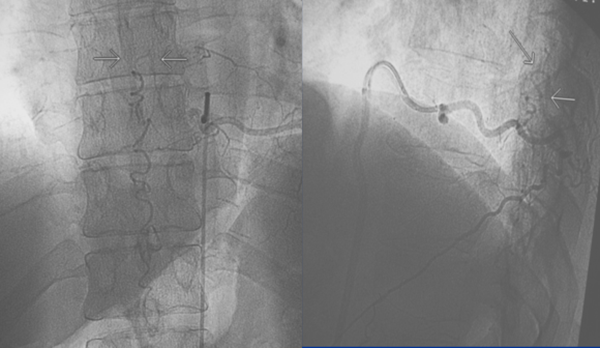

Figura 7: Caso #1. Vista intraoperatoria. A la izquierda: se observa la vena de drenaje (flecha) emerger de la cara lateral de la duramadre, llega a la línea media posterior de la médula y continúa hacia abajo en forma serpiginosa. En el centro: la coagulación de la vena de drenaje. A la derecha: se observa la vena seccionada.

Figura 8: Caso #1. ADM postoperatoria alejada que demuestra la ausencia de la FDAVE en D8 izq.

Figura 11: Caso #2. Vista final intraoperatoria. En este caso se coaguló la vena de drenaje y se adicionaron 2 haemoclips.